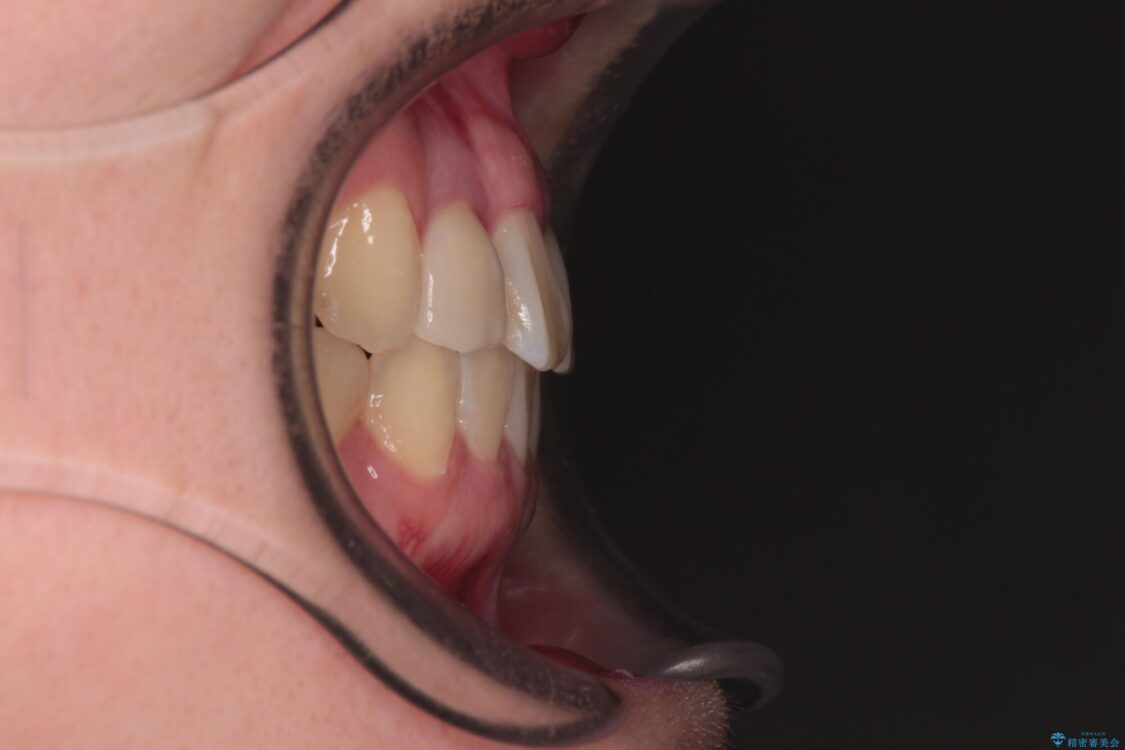

治療後

• 虫歯治療ついでに歯並びの後戻りを改善 インビザラインによる矯正治療 治療後画像